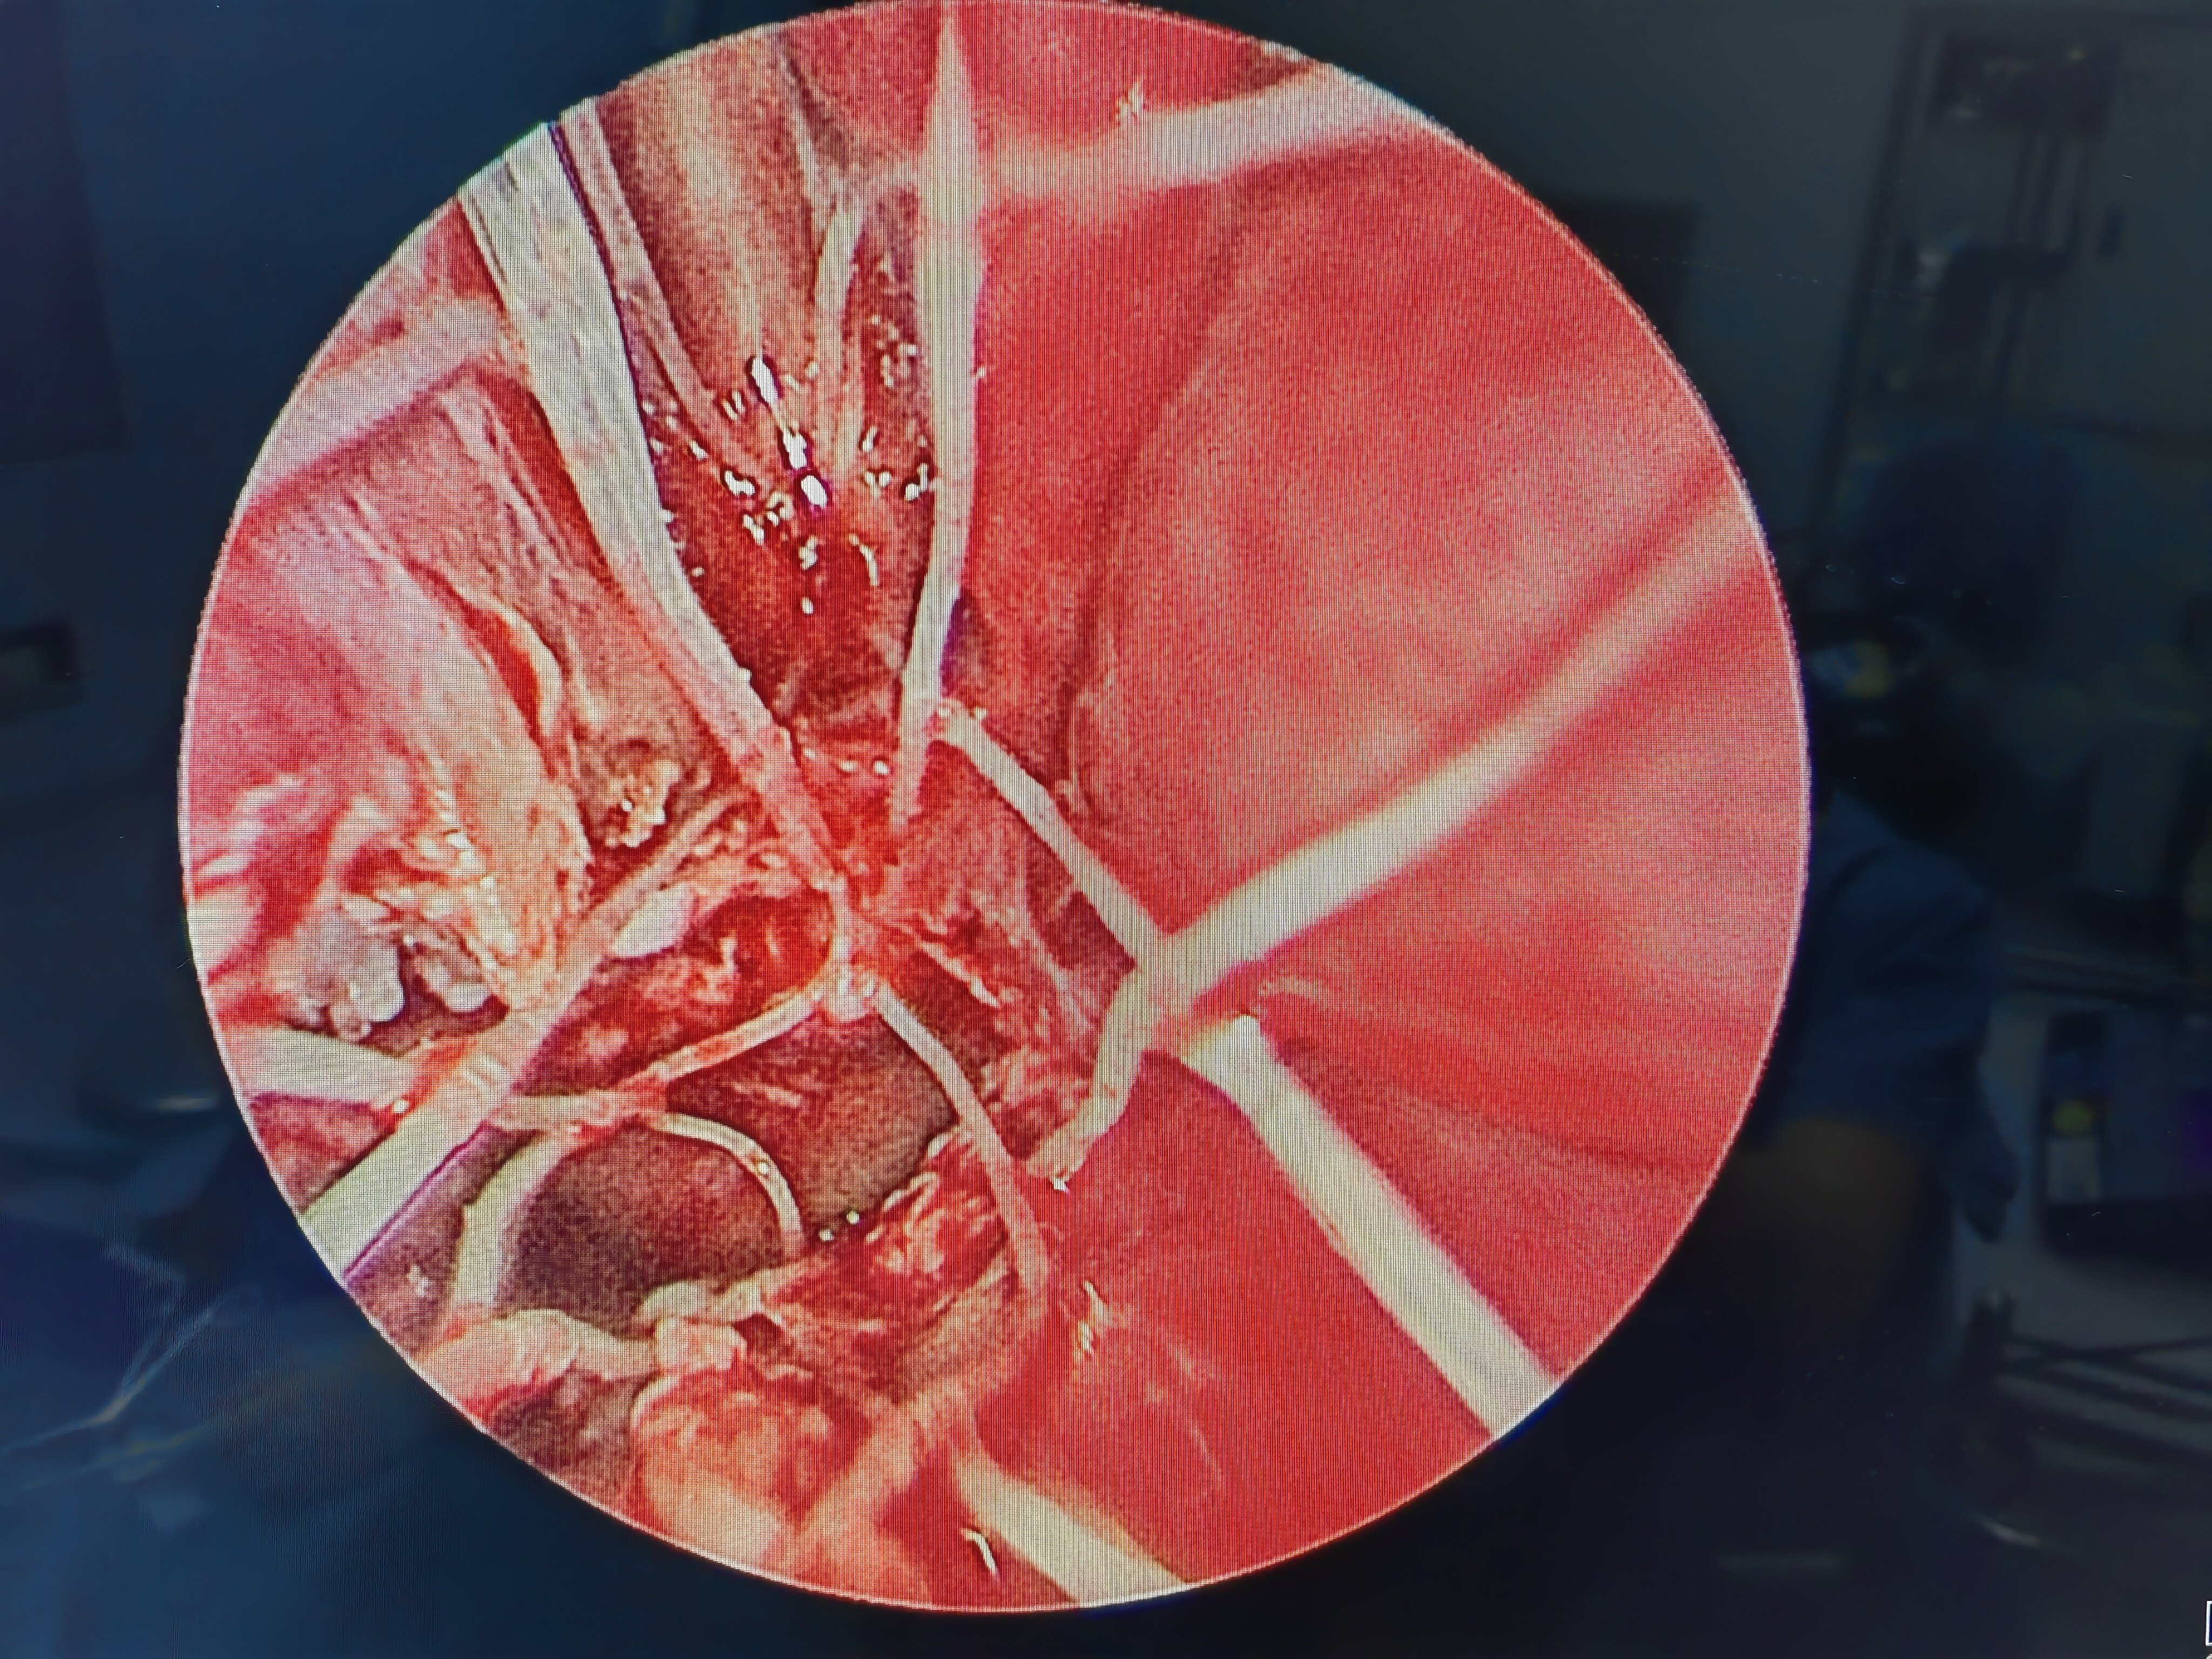

双侧闭锁板切除+鼻中隔后端切除后 术中